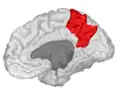

![]() Sagittal MRI slice with the precuneus shown in red. (Anterior to the left.) | |

Precuneus of left cerebral hemisphere (shown in red).